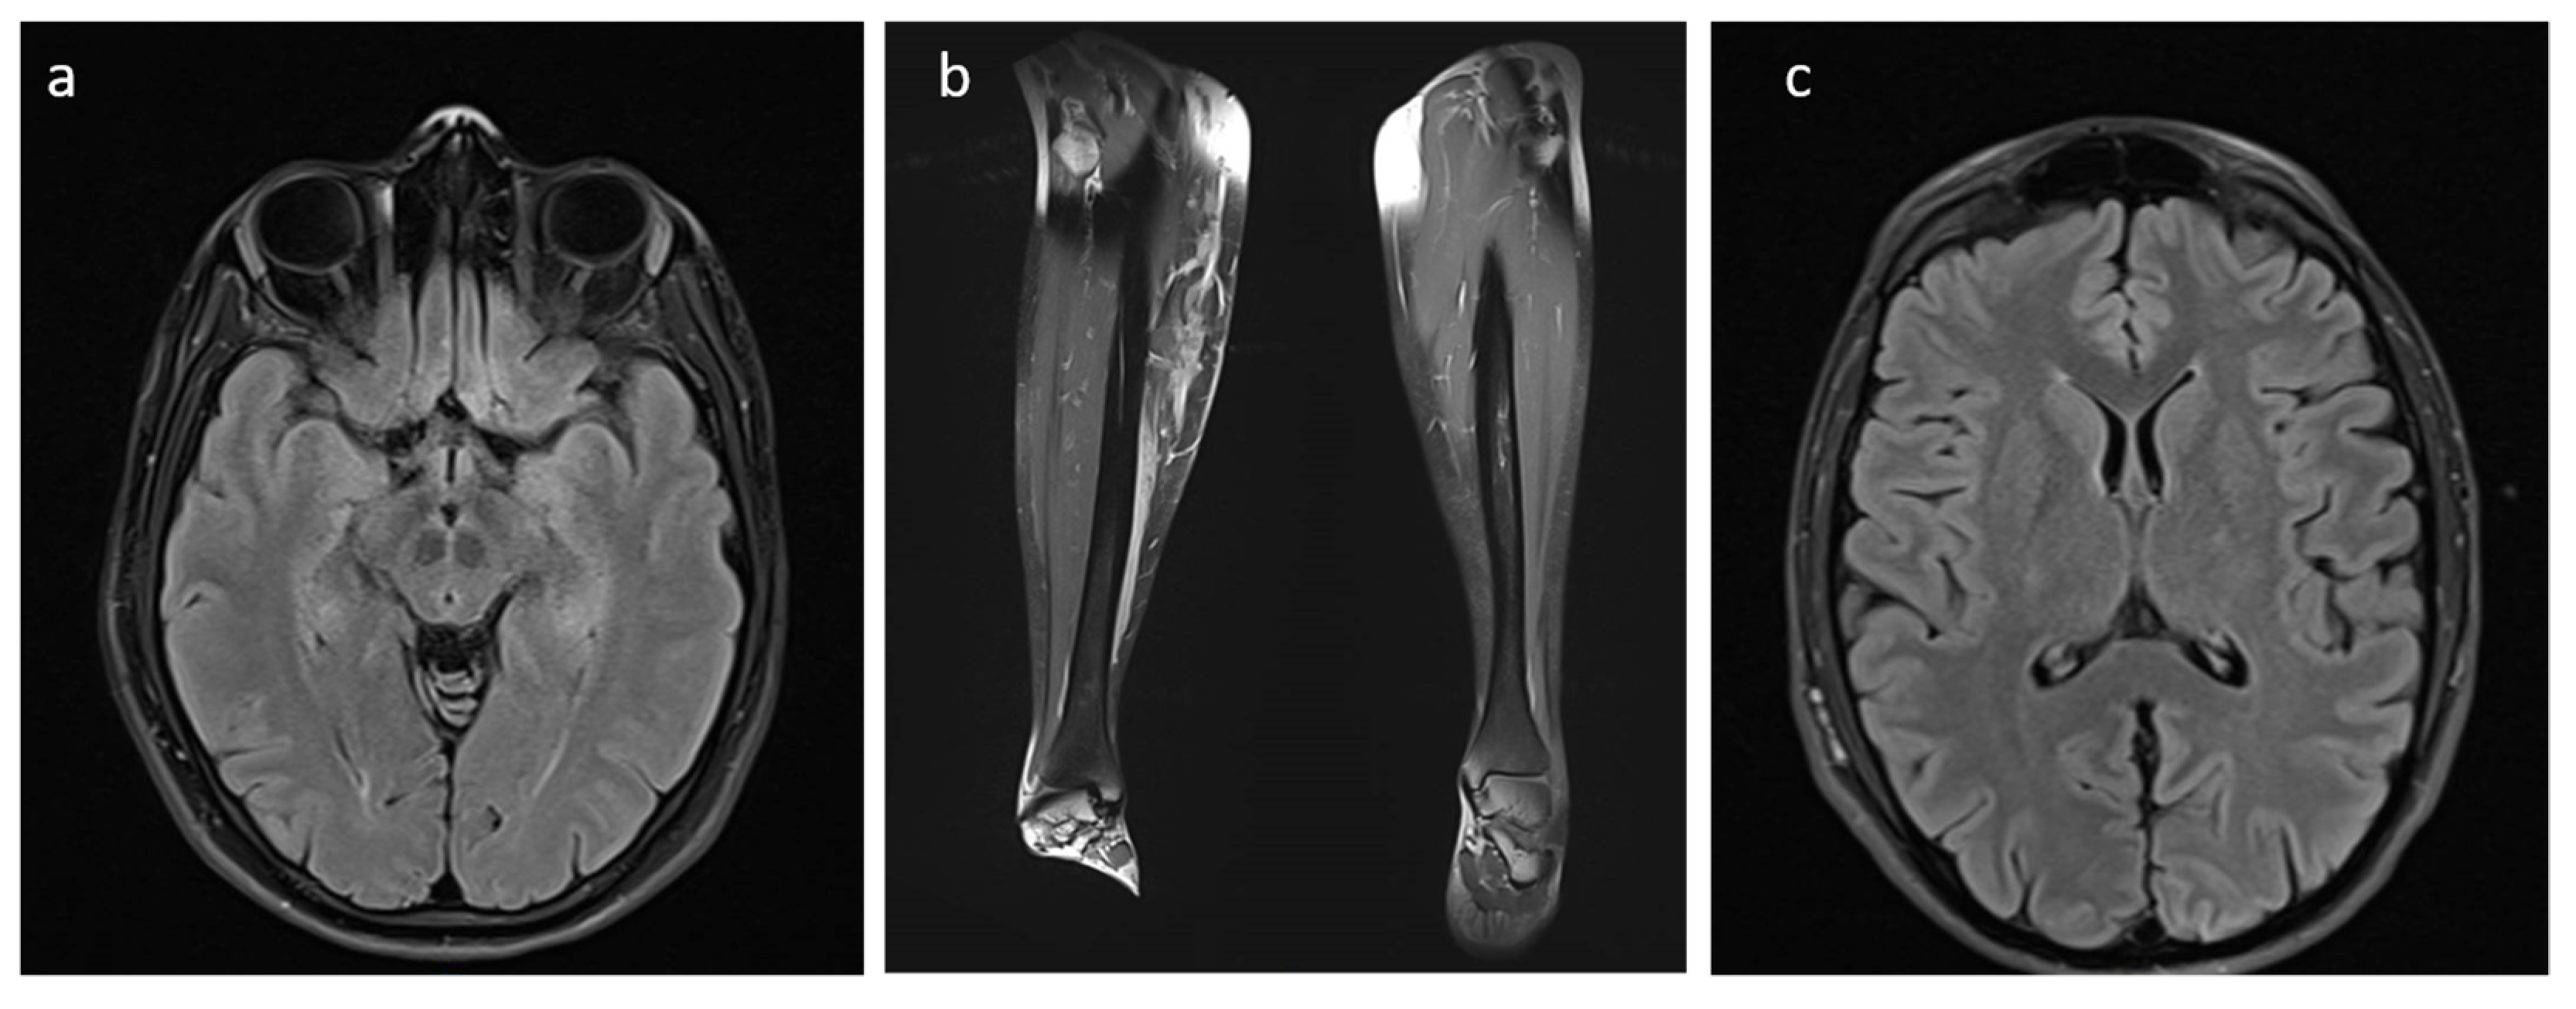

2.1. Clinical Description